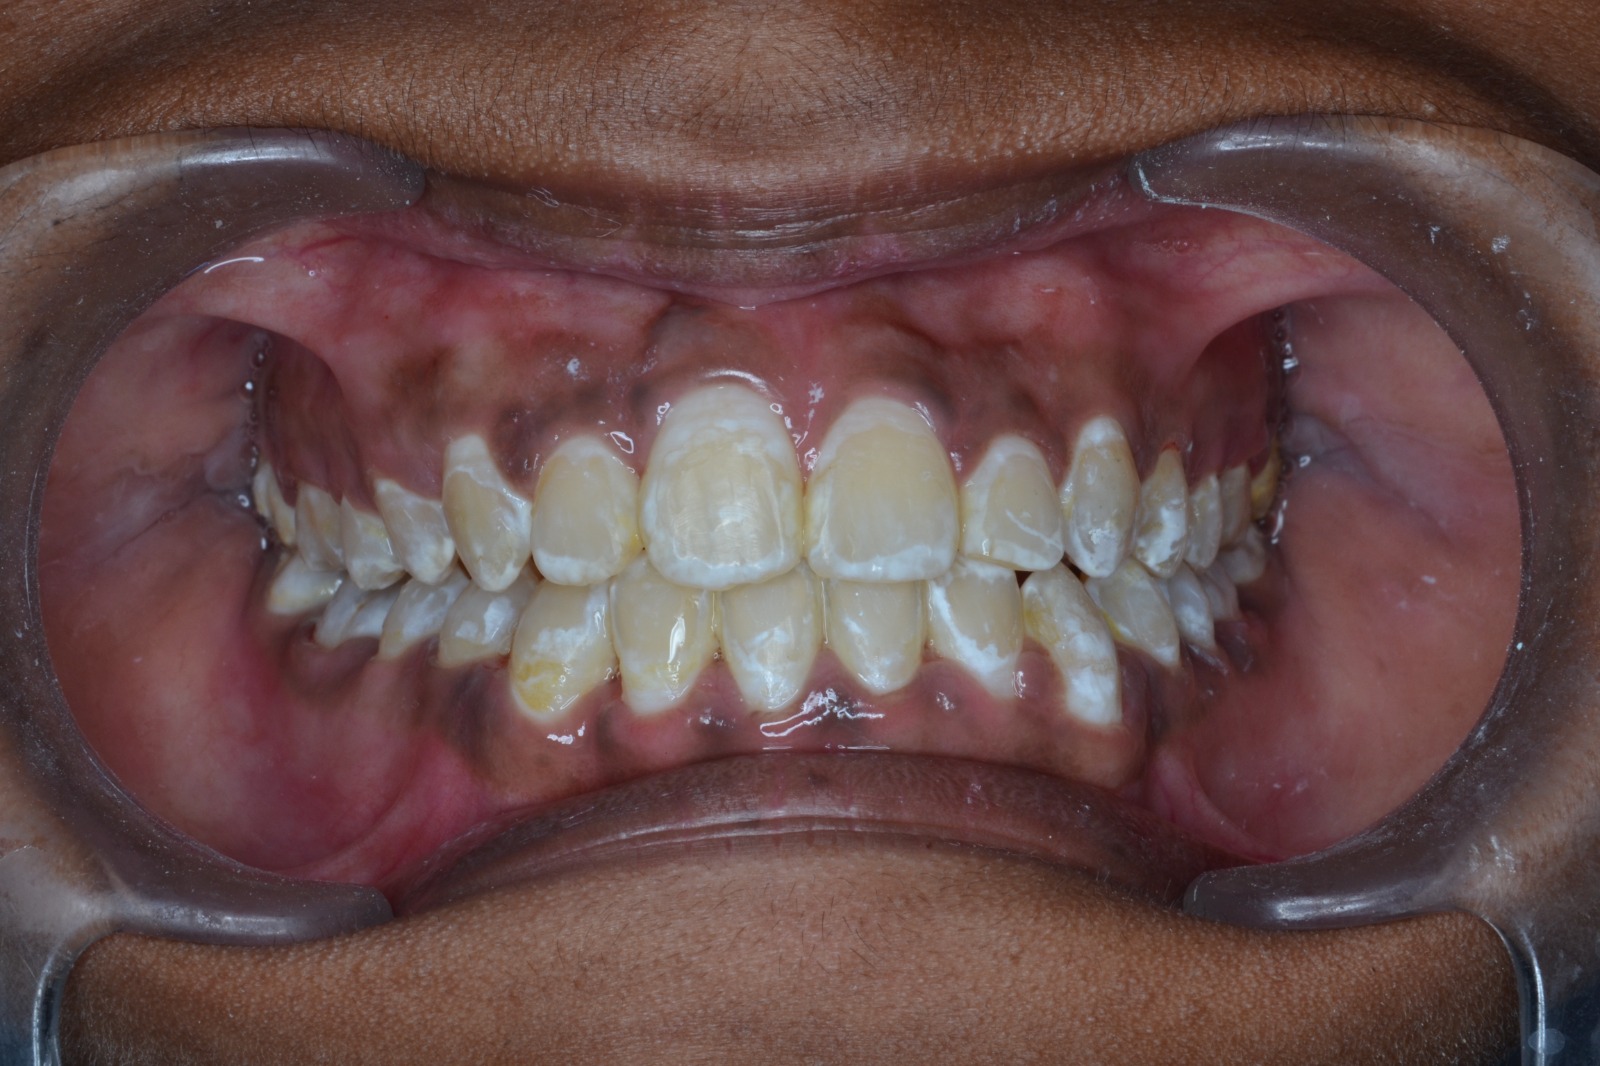

After/Before

See stunning smile transformation before and after

Before After